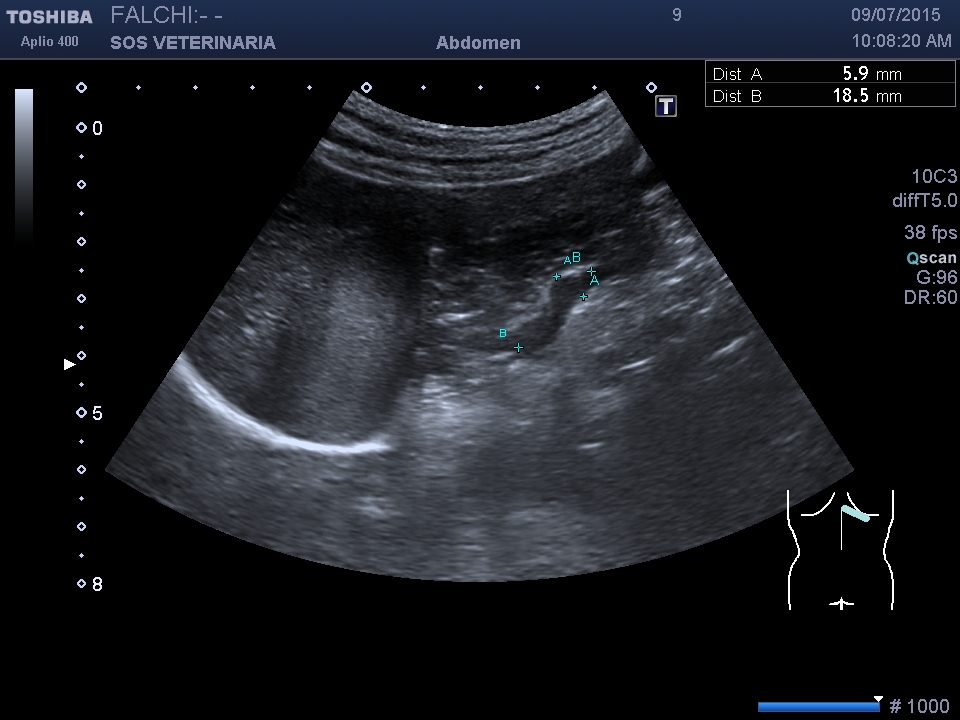

controllo dopo 4 mesi

la lesione e’ cresciuta, il cane sotto somministrazione di vetoryl e’ migliorato nei sintomi dell’ipercorticosurrenalismo ,bene sul piano generale viene visto solo per un controllo

la prima ecografia asse maggiore 3,5 cm

la seconda dopo 2 mesi asse maggiore 4,2 cm